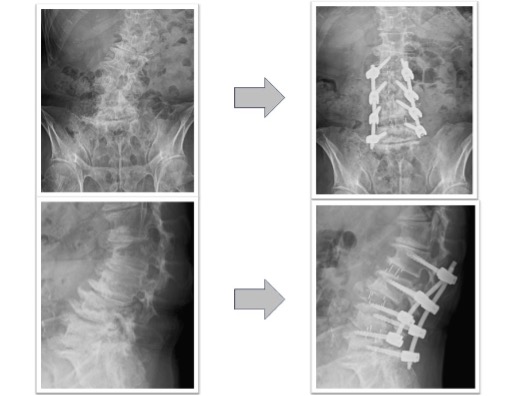

変性側弯を伴う多椎間の椎間板ヘルニア、脊柱管狭窄症(図3,4)

下肢痛、歩行障害、腰痛で来院、手術となりました。術前後のレントゲンで3椎間のOLIFによって術後側弯症が改善され、脊椎の並び(アライメント)が矯正されています(図3)。また、術前後のMRIでは施術した部位の椎間板ヘルニアおよび脊柱管狭窄がOLIFの間接除圧効果によって改善し、神経への圧迫が解除されています(図4)。術後は歩行可能、下肢痛腰痛も改善、また結果として数センチ身長が回復しています。

図3

図4